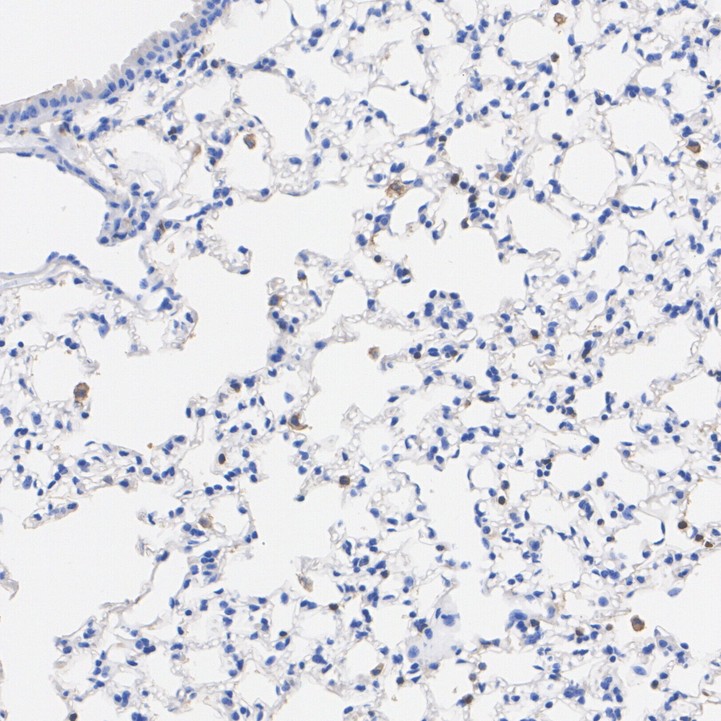

Immunohistochemical analysis of paraffin-embedded mouse lung tissue with Mouse anti-F4/80 antibody (HA601537) at 1/2,000 dilution.

The section was pre-treated using heat mediated antigen retrieval with Tris-EDTA buffer (pH 9.0) for 20 minutes. The tissues were blocked in 1% BSA for 20 minutes at room temperature, washed with ddH2O and PBS, and then probed with the primary antibody (HA601537) at 1/2,000 dilution for 1 hour at room temperature. The detection was performed using an HRP conjugated compact polymer system. DAB was used as the chromogen. Tissues were counterstained with hematoxylin and mounted with DPX.